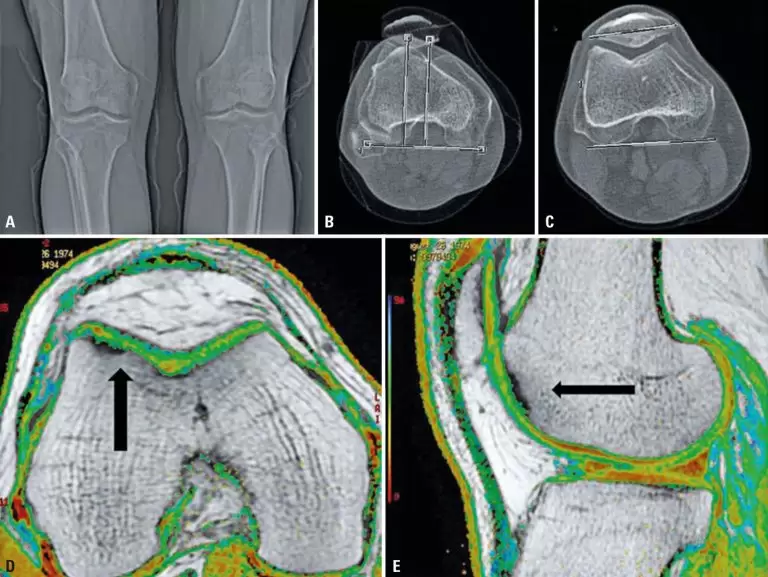

ABSTRACT To describe a case of autologous chondrocyte implantation after cell culture contamination by Mycoplasma pneumoniae and the measures taken to successfully complete cell therapy in a patient with focal chondral lesion. A 45-year-old male patient, complaining of chronic pain on the knee and no history of trauma. He had a chondral lesion in the trochlear region of the femur and clinical tests compatible with pain in the anterior compartment of the knee. Conservative treatment failed to alleviate symptoms. Surgical […]